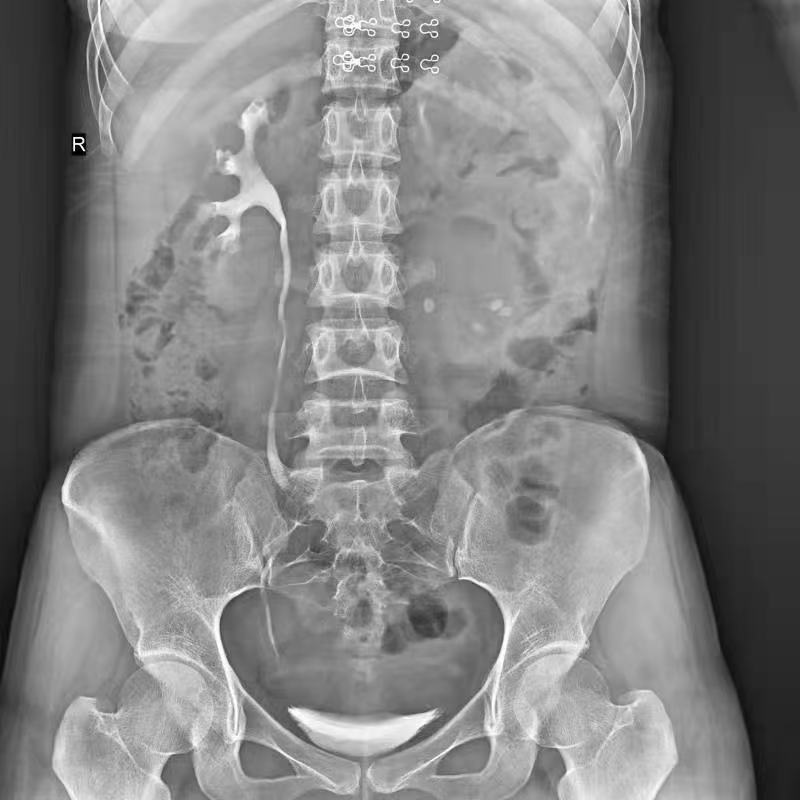

●呈現(xiàn)全下肢或全脊柱圖像

●在脊柱及下肢畸形矯正手術(shù)治療中,為術(shù)前方案制定和術(shù)后復(fù)查提供精準(zhǔn)測量

●有效解決傳統(tǒng)X光片不能一次成像問題,為患者提供更加優(yōu)質(zhì)的醫(yī)療服務(wù)